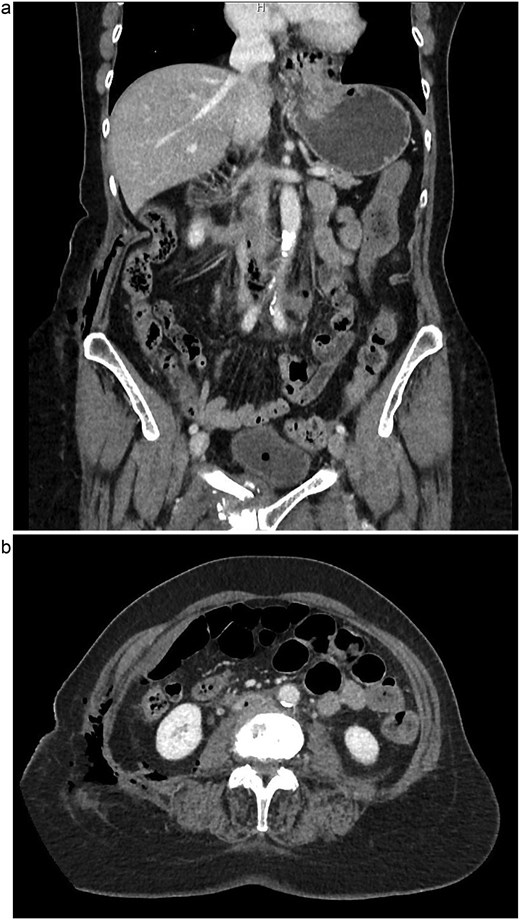

The patient is a 75-year-old female with no relevant past medical or surgical history who underwent an L4-L5 extreme lateral interbody fusion (XLIF) at an outside surgical center. During the procedure, a significant amount of blood loss from an undetermined bleeding vessel was encountered. The primary surgeon injected Surgiflo and Gelfoam to attempt to obtain hemostasis. The XLIF was completed with an estimated blood loss of greater than 2 l. In the post-anesthesia care unit (PACU), the patient remained hypotensive. Two units of packed red blood cells, phenylephrine, 5 l of crystalloid, and 50 g of albumin were administered in the PACU and the patient was transferred to a surgical intensive care unit at a level one trauma center. A computed tomography (CT) scan was obtained which demonstrated a thrombus present in the inferior vena cava (IVC) extending to the left common iliac vein (Fig. 1a and b). She received an additional unit of packed red blood cells and blood pressure support was maintained with norepinephrine. Vascular surgery was consulted. At the time of evaluation, the patient had remarkably improved hemodynamics and was on minimal pressor support. After discussion of risks and benefits of intervention versus medical management, the vascular team recommended therapeutic anticoagulation with continuous intravenous heparin. The patient was observed in the intensive care unit for 2 days until she was off pressor support. She was started on apixaban once her hemoglobin was stable on three consecutive blood draws. A repeat CT angiogram 1 month after discharge demonstrated near resolution with a small residual thrombus in the left common iliac vein (Fig. 2a and b). She has returned to normal activity and will remain on apixaban for 6 months after the inciting event and the thrombus will be evaluated again for further evolution.

(a) Coronal view of thrombus and air in IVC, initial imaging. (b) Axial view of thrombus and air in IVC, initial imaging.